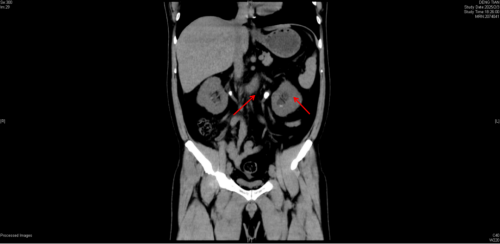

术前CT片显示双侧肾结石、双输尿管结石导致双肾积水